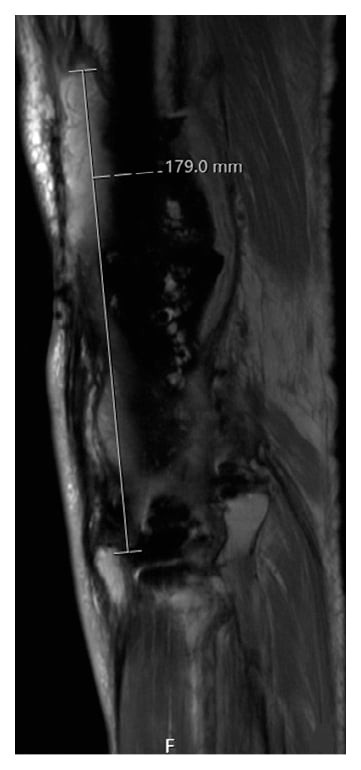

Recurrent PJI suspected 2 months later was treated with IV vancomycin and then oral doxycycline, although cultures remained negative. The patient reported persistent swelling of the leg, but no fevers, chills, or wound issues. The left knee subsequently grew Aspergillus flavus a year later, treated with DFR reimplantation and soft tissue reconstruction by way of a medial gastrocnemius muscle flap. Nonetheless, the infection persisted, and a static antibiotic eluting hip-knee-ankle fusion nail spacer (Figure 2) was inserted, with continuous voriconazole treatment.

Figure 2: Postoperative EOS X-ray showing static antibiotic eluting hip-knee-ankle fusion nail spacer.

On examination, the patient walked with a cane but reported that his pain had subsided and he had no body aches, fever, chills, or knee swelling. The left knee demonstrated mild edema, with no erythema or signs of persistent infection. Left knee X-ray revealed well-positioned intramedullary hip-knee-ankle fusion nail without movement of the proximal or distal interlocking screws. Magnetic resonance imaging (MRI) revealed fluid surrounding the cement spacer, distending the joint capsule (Figure 3). Preoperative laboratory results included a white blood cell (WBC) count of 8.5/nL (neutrophils 67.5%, lymphocytes 15.7%), erythrocyte sedimentation rate of 58 mm/hr, and C-reactive protein of 2.2 mg/dL. Synovial fluid culture showed Aspergillus flavus infection of the multiply revised TKA. The patient could not perform activities of daily living with the fusion nail in place and was indicated for conversion to DFR.

Figure 3: Preoperative MRI showing bone marrow edema and joint fluid surrounding the cement spacer, distending the joint capsule 18 cm proximal to distal.